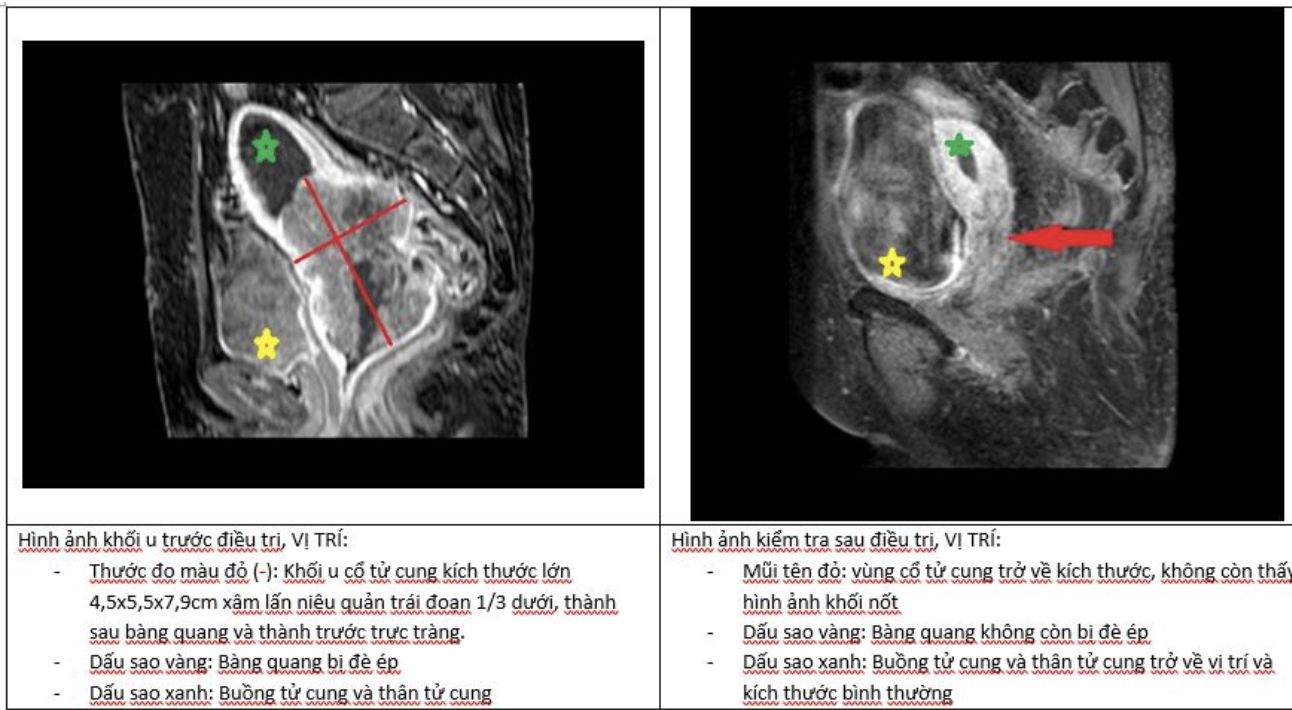

Hình ảnh sau 4 tháng điều trị (ảnh BSCC).

Sau khi thăm khám, làm đầy đủ xét nghiệm và chẩn đoán hình ảnh, bác sĩ đã xây dựng một phác đồ điều trị đa mô thức: xạ trị chiếu ngoài kết hợp với hóa trị hàng tuần, sau đó tiếp tục xạ trị áp sát – một kỹ thuật hiện đại cho phép đưa liều xạ trực tiếp vào vùng tổn thương, giúp tăng hiệu quả điều trị và giảm ảnh hưởng lên các mô lành xung quanh.

Sau hơn 4 tháng bệnh nhân kiên trì điều trị theo phác đồ, kết quả tái khám cho thấy khối u không còn xuất hiện, các hình ảnh chẩn đoán đều bình thường.